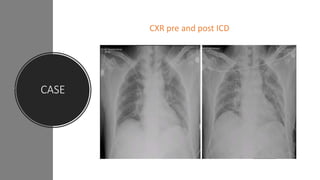

CASE

BREATHING – Spontaneous ;RR-20/Min , SPO2-100%;

Chest – Decreased Air Entry Lt Side;

CCT- Positive

Pnemo Scan- Negative

Left sided ICD was inserted in 5th ICS under LA ,

gush of air and minimal blood with good column

movemnt

CXR pre and post ICD